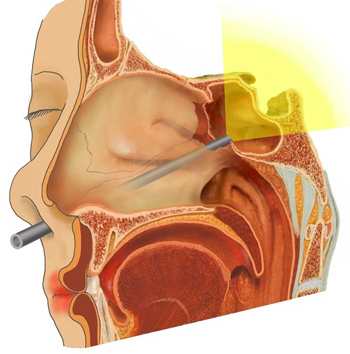

• 図1.内視鏡を用いた下垂体手術

内視鏡を鼻腔の奥に入れることでより広い範囲の観察が可能です。

近年の普及が最もめざましいのは下垂体の手術です(図1)。下垂体という両眼の奥にある場所に、狭くて奥行きのある鼻腔からでも内視鏡を用いてアプローチすることで広い視野角で観察し全体を良く見ながら摘出することができるため摘出率が向上しています。また、手術の際の鼻の粘膜の損傷も少なくなる場合が多くなります。